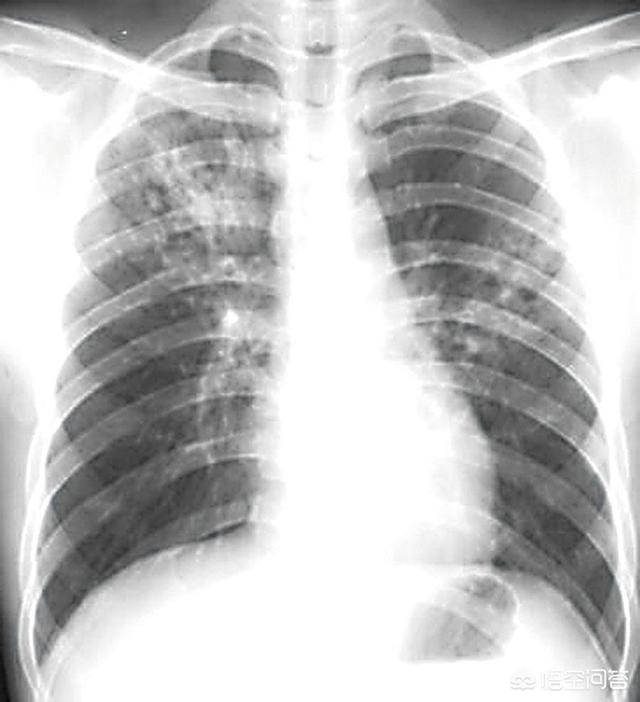

确实随地吐痰仍然是很多身边人常有的恶习,也是我国结核病一直控制不好的重要原因之一,肺结核等传染性疾病在人群中相互传播的重要途径就是痰液传播,结核菌在阴暗角落里的痰液中可以存活2个月,在这两个月内,所有路过的人都有可能被传染,一般肺结核的感染有一定的潜伏期,也就是从人感染了结核菌一直到结核繁殖生长成足以引起症状的病灶是有一个时间的,大部分结核患者会有咳嗽,咳白痰,午后低热,消瘦乏力,食欲不振等症状,严重的可有高热,咯血等。

3、结核病发病后早期症状

咳嗽咳痰,低热,以午后低热为主,体温一般在37-38℃之间,乏力,食欲减退,夜间盗汗等症状。并非每个人都会有这些典型的症状。

4、结核病的诊断

目前的诊断主要取决于痰内是否有结核分枝杆菌。痰液抗酸染色找结核菌,如果阳性,说明痰液内有大量的结核细菌。如果痰抗酸染色阴性,但是在痰液内找到结核分枝杆菌核酸,也能说明痰液里有结核菌,只是数量较少。